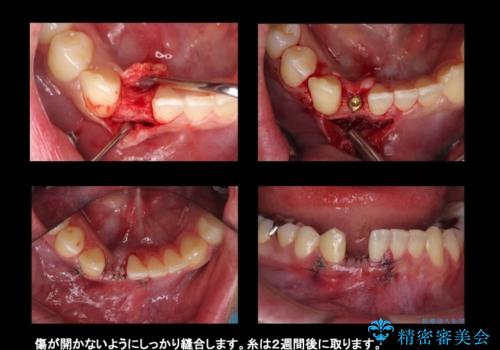

- 下の前歯が1本生まれつき少なかったため、インプラント治療を行いました。

インプラントの前に矯正治療を行い、入れる隙間を確保しました。

- 45万円(税別) 内訳:ストローマンインプラント(1本)20万円、ジルコニアクラウン10万円、シリンダーTeC 2万円 ジルコニアカスタムアバットメント10万円 ホワイトニング(エクセレント)3万円費用は治療当時の料金となります

ブリッジにすることも可能でしたが、両側の歯が天然歯であること、また、事前に矯正で噛み合わせを整え、幅も確保していたこと、CTにより骨の厚みがある程度あったことを踏まえ、インプラントも可能であるとお話しし、選んでいただきました。

唇側の骨増成もしっかり行い、前歯部インプラントによくある、歯茎が下がって見えることもない、審美的なインプラント補綴ができました。